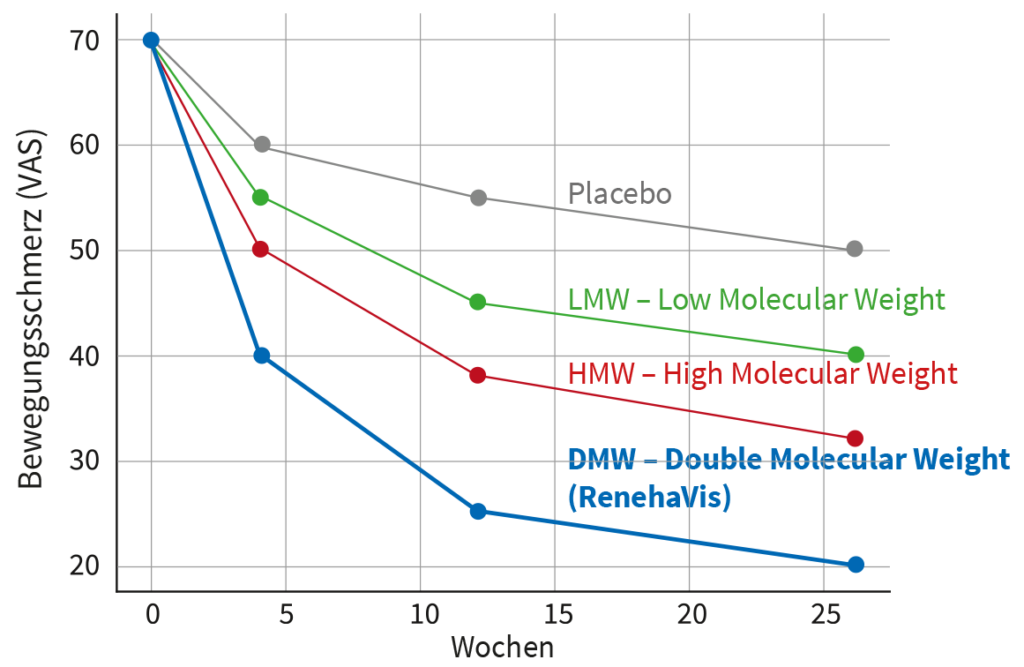

Der RenehaVis-Vorteil

RenehaVis funktioniert und reduziert Ihre Schmerzen wirksamer als mono-molekulare Hyaluronsäuren (LMW und HMW) – (1)

Bewegungsschmerz bei Kniearthrose – Vergleich verschiedener HA-Präparate

Patienten berichteten unter RenehaVis über eine signifikant höhere Zufriedenheit mit der Therapie. (1)

(1) PROF. DR. ROBERT PETRELLA. UNIVERSITY OF WESTERN ONTARIO Zur Studie